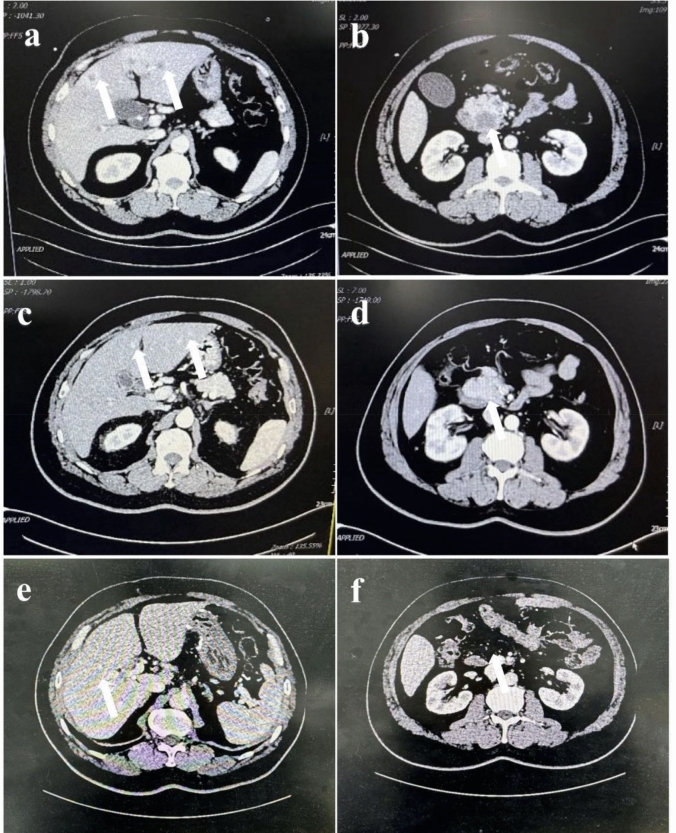

Case presentation: A 52-year-old male patient with pancreatic cancer and multiple liver metastases was reported. Imaging examination showed multiple low-density shadows in the liver. Laboratory tests showed elevated levels of pro-gastrin-releasing peptide and CEA. After gemcitabine combined with albumin-bound paclitaxel chemotherapy, the liver metastases disappeared and the primary pancreatic head tumor was significantly reduced. Pancreaticoduodenectomy was performed, and the patient recovered well without any other adjuvant therapy. The patient has been alive for 36 months without tumor recurrence.